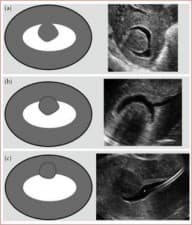

Reproductive medicine is a field of medicine that deals with the prevention, diagnosis, and management of male and female reproductive issues. It encompasses the prevention and assessment, as well as the treatment and prognosis of a wide variety of reproductive conditions. The main goal of reproductive medicine is to improve or maintain the female and male reproductive systems. Reproductive medicine specialists particularly treat and advise on any issues impacting a person’s or a couple’s ability to conceive. They treat issues of puberty, sexual education, family planning, birth control, infertility, sexual dysfunction, and reproductive system disease, such as:

Tests and treatments that reproductive medicine may perform include:

Reproductive medicine is a multidisciplinary branch of medicine that combines physiology, endocrinology, and anatomy, as well as some aspects of biochemistry and molecular biology. Reproductive medicine also overlaps with other branches of medicines, such as gynecology, urology, obstetrics, and psychiatry.